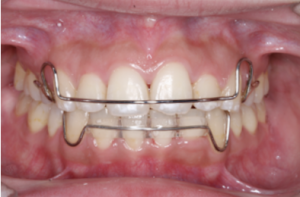

リテーナーの場合には透明なマウスピース型を使用する場合もあれば、ワイヤーとレジンで作られたプレート型を使用する場合もあります。

プレート型のリテーナー